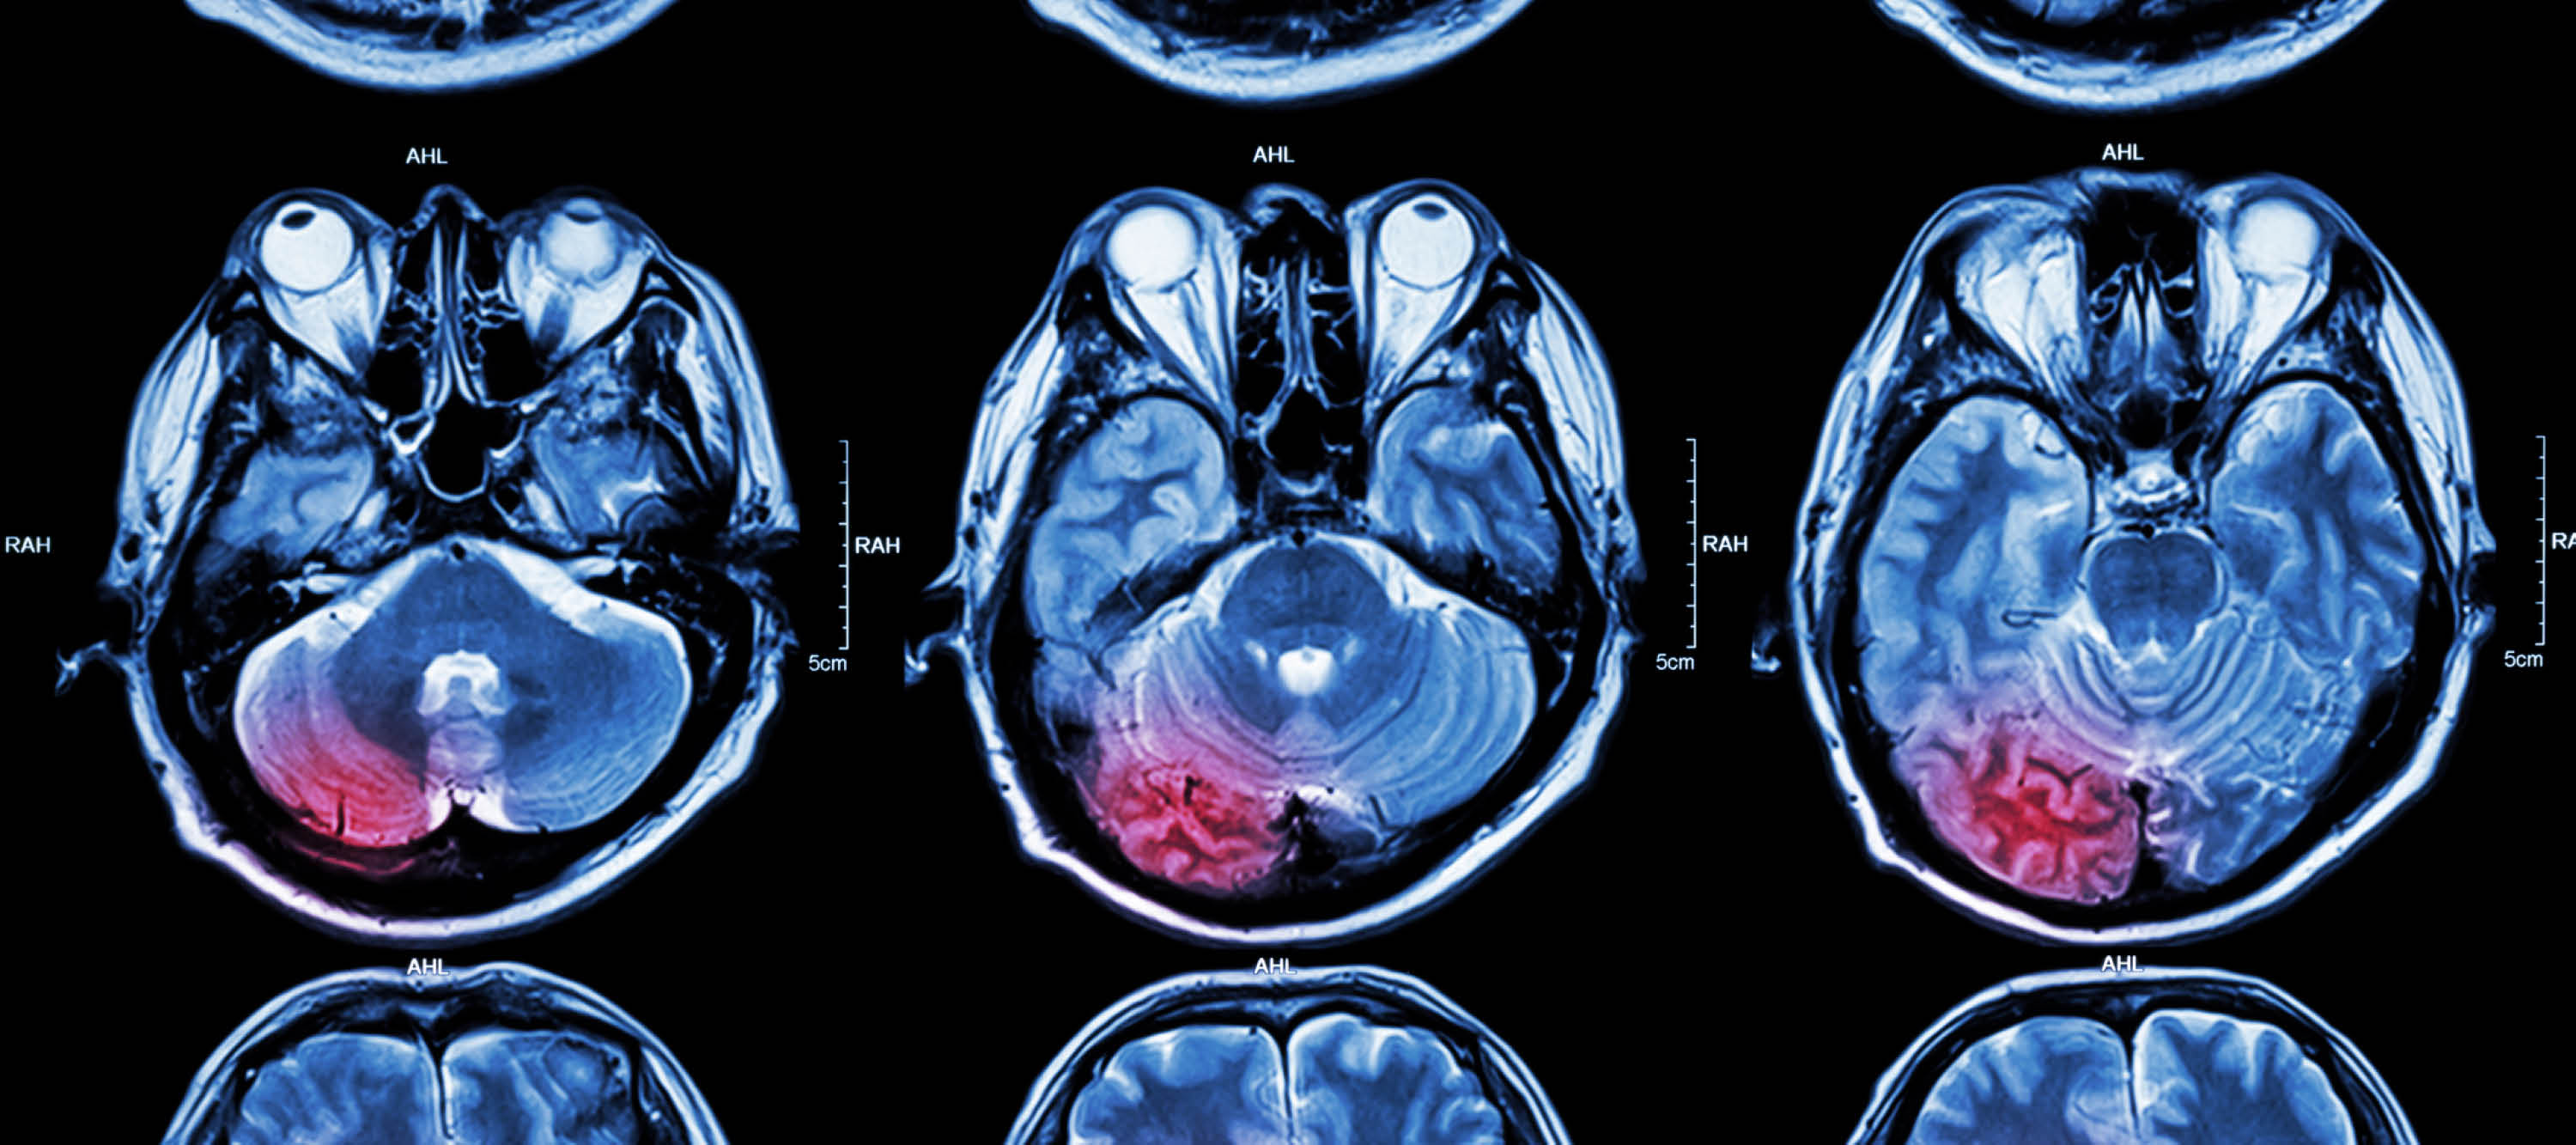

I-TeleRAD’s dedicated urgent stroke reporting service includes the provision of perfusion imaging to treating teams using RAPID AI. Treating clinicians and radiology departments can contact us directly on the dedicated stroke phone number below. Treating teams will receive perfusion images via email or portal within 10 minutes of the scan arriving at I-TeleRAD.